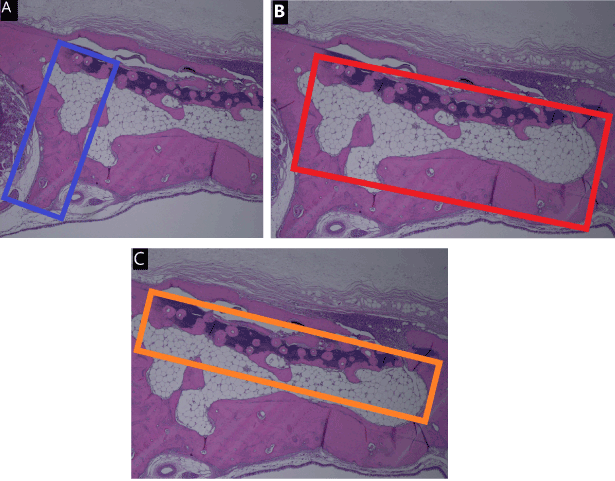

New bone formation was evaluated in an area demarcated by an arbitrarily selected 1-mm segment within the irradiated zone and a parallel straight line 3 mm from it. The ratio of soft tissue was determined based on an area surrounding a 4-mm diameter of the irradiated zone and a parallel straight line drawn between the native bone 2 mm from it. The ratio of soft necrosis was determined based on an area surrounding the 4-mm diameter of the irradiated zone and a parallel straight line drawn between the native bone 1 mm from it (Figure 3A-C).

Figure 3. Description of the methods of histometric analysis. New bone formation was evaluated in an area demarcated by an arbitrarily selected 1-mm segment within the irradiated zone and a parallel straight line 3 mm from it (A). The ratio of soft tissue was determined based on an area surrounding a 4-mm diameter of the irradiated zone and a parallel straight line drawn between the native bone 2 mm from it (B). The ratio of soft necrosis was determined based on an area surrounding the 4-mm diameter of the irradiated zone and a parallel straight line drawn between the native bone 1 mm from it (C)